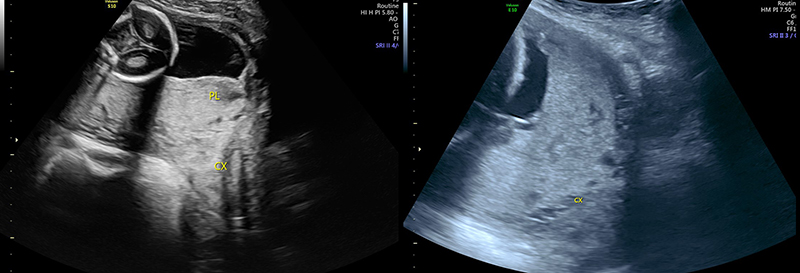

Figure 35. Sagittal transabdominal view of the pelvis revealing the anechoic urinary bladder (BL) and a normal cervix (CX) just below.

Figure 36. Sagittal transabdominal view of the pelvis similar to Figure (prior), with hyperechoic placenta (PL) covering the internal cervical os (CX).